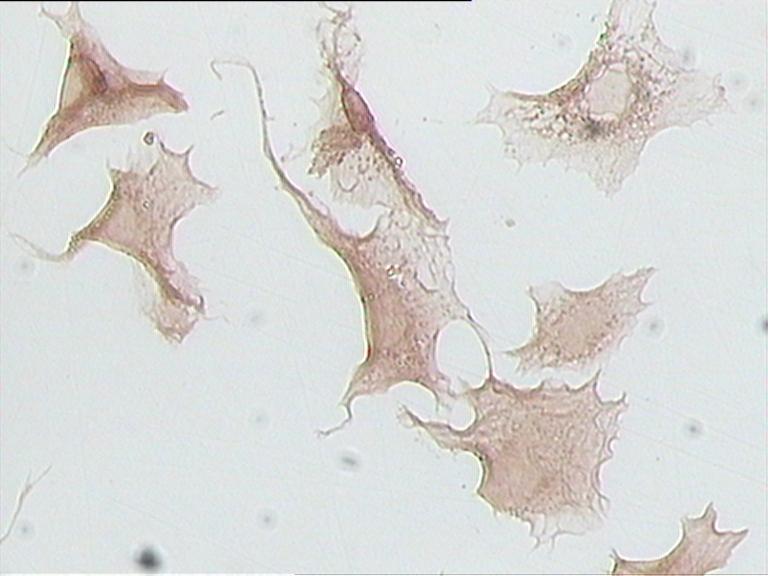

免疫組化【細(xì)胞染色】

對照組

目的蛋白1

目的蛋白2